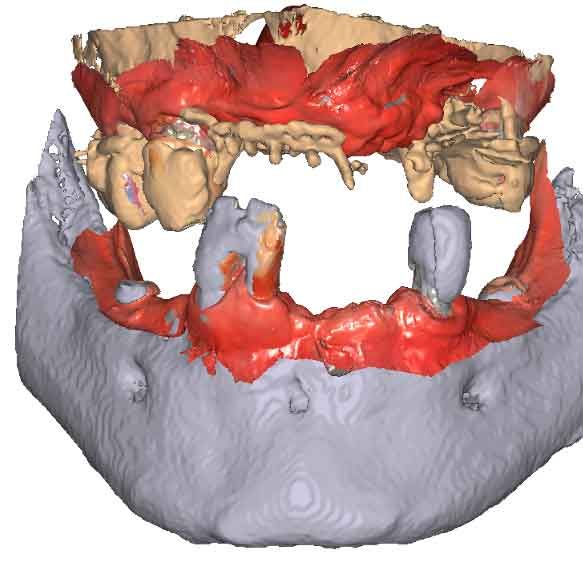

étape 2 – Acquisition du CBCT

Lorsque les scans IOS traditionnels manquent de références nécessaires, les données du CBCT peuvent servir d'alternative viable. En utilisant les fichiers du CBCT, le clinicien peut établir des références anatomiques précises pour la planification du traitement.

Pour pouvoir utiliser les données CBCT comme modèles initiaux, nous devons transformer le fichier DICOM en un fichier STL. Découvrez-en plus sur la segmentation CBCT et son utilisation dans TWIM ci-dessous.

En important les fichiers DICOM du patient au lieu des scans IOS, les cliniciens peuvent enregistrer le mouvement de la mâchoire, facilitant ainsi la planification précise du traitement.

Importez les modèles CBCT segmentés en tant que modèles initiaux dans TWIM

Sélectionnez 4 points virtuels sur la mandibule du modèle osseux importé